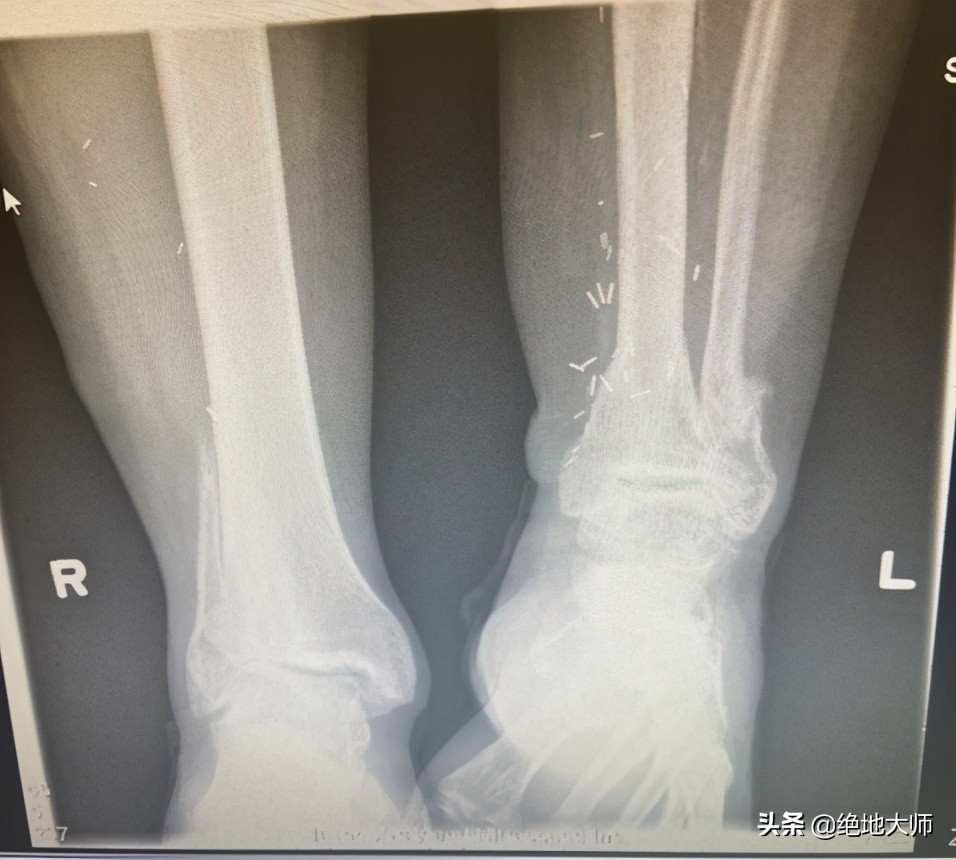

4. Structural LLD 结构性腿长不等

右侧腓骨缺失,左侧应力性骨折。

6. Structural LLD causes DJD, fracture 结构性LLD导致退行性关节病变、骨折